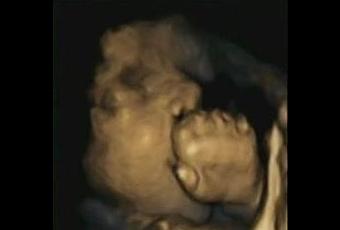

Les scientifiques de Durham et de l’université de Lancaster ont réalisé 60 « balayages » ou scans de 15 fœtus sains, chaque mois, entre 24 et 36 semaines de grossesse. Ils montrent, à partir de ces images 4D, que le fœtus dans les stades précoces de la grossesse touche plus souvent la partie supérieure et les côtés de la tête mais que, peu à peu au fil de la grossesse, le fœtus commence à toucher de plus en plus la partie inférieure de son visage dont sa bouche (Sur les visuels, à 32 semaines). Enfin, dans les derniers stades, le fœtus est en mesure de prédire, -au-delà de réagir à- ses propres mouvements de la main vers la bouche.

Cette augmentation progressive de la sensibilité autour de la bouche d’un fœtus au stade tardif de la grossesse pourrait signifier que le bébé a acquis une certaine « sensibilisation » des mouvements de la bouche et constituer un indicateur potentiel de la façon dont les bébés sont préparés (ou non) à l’alimentation.